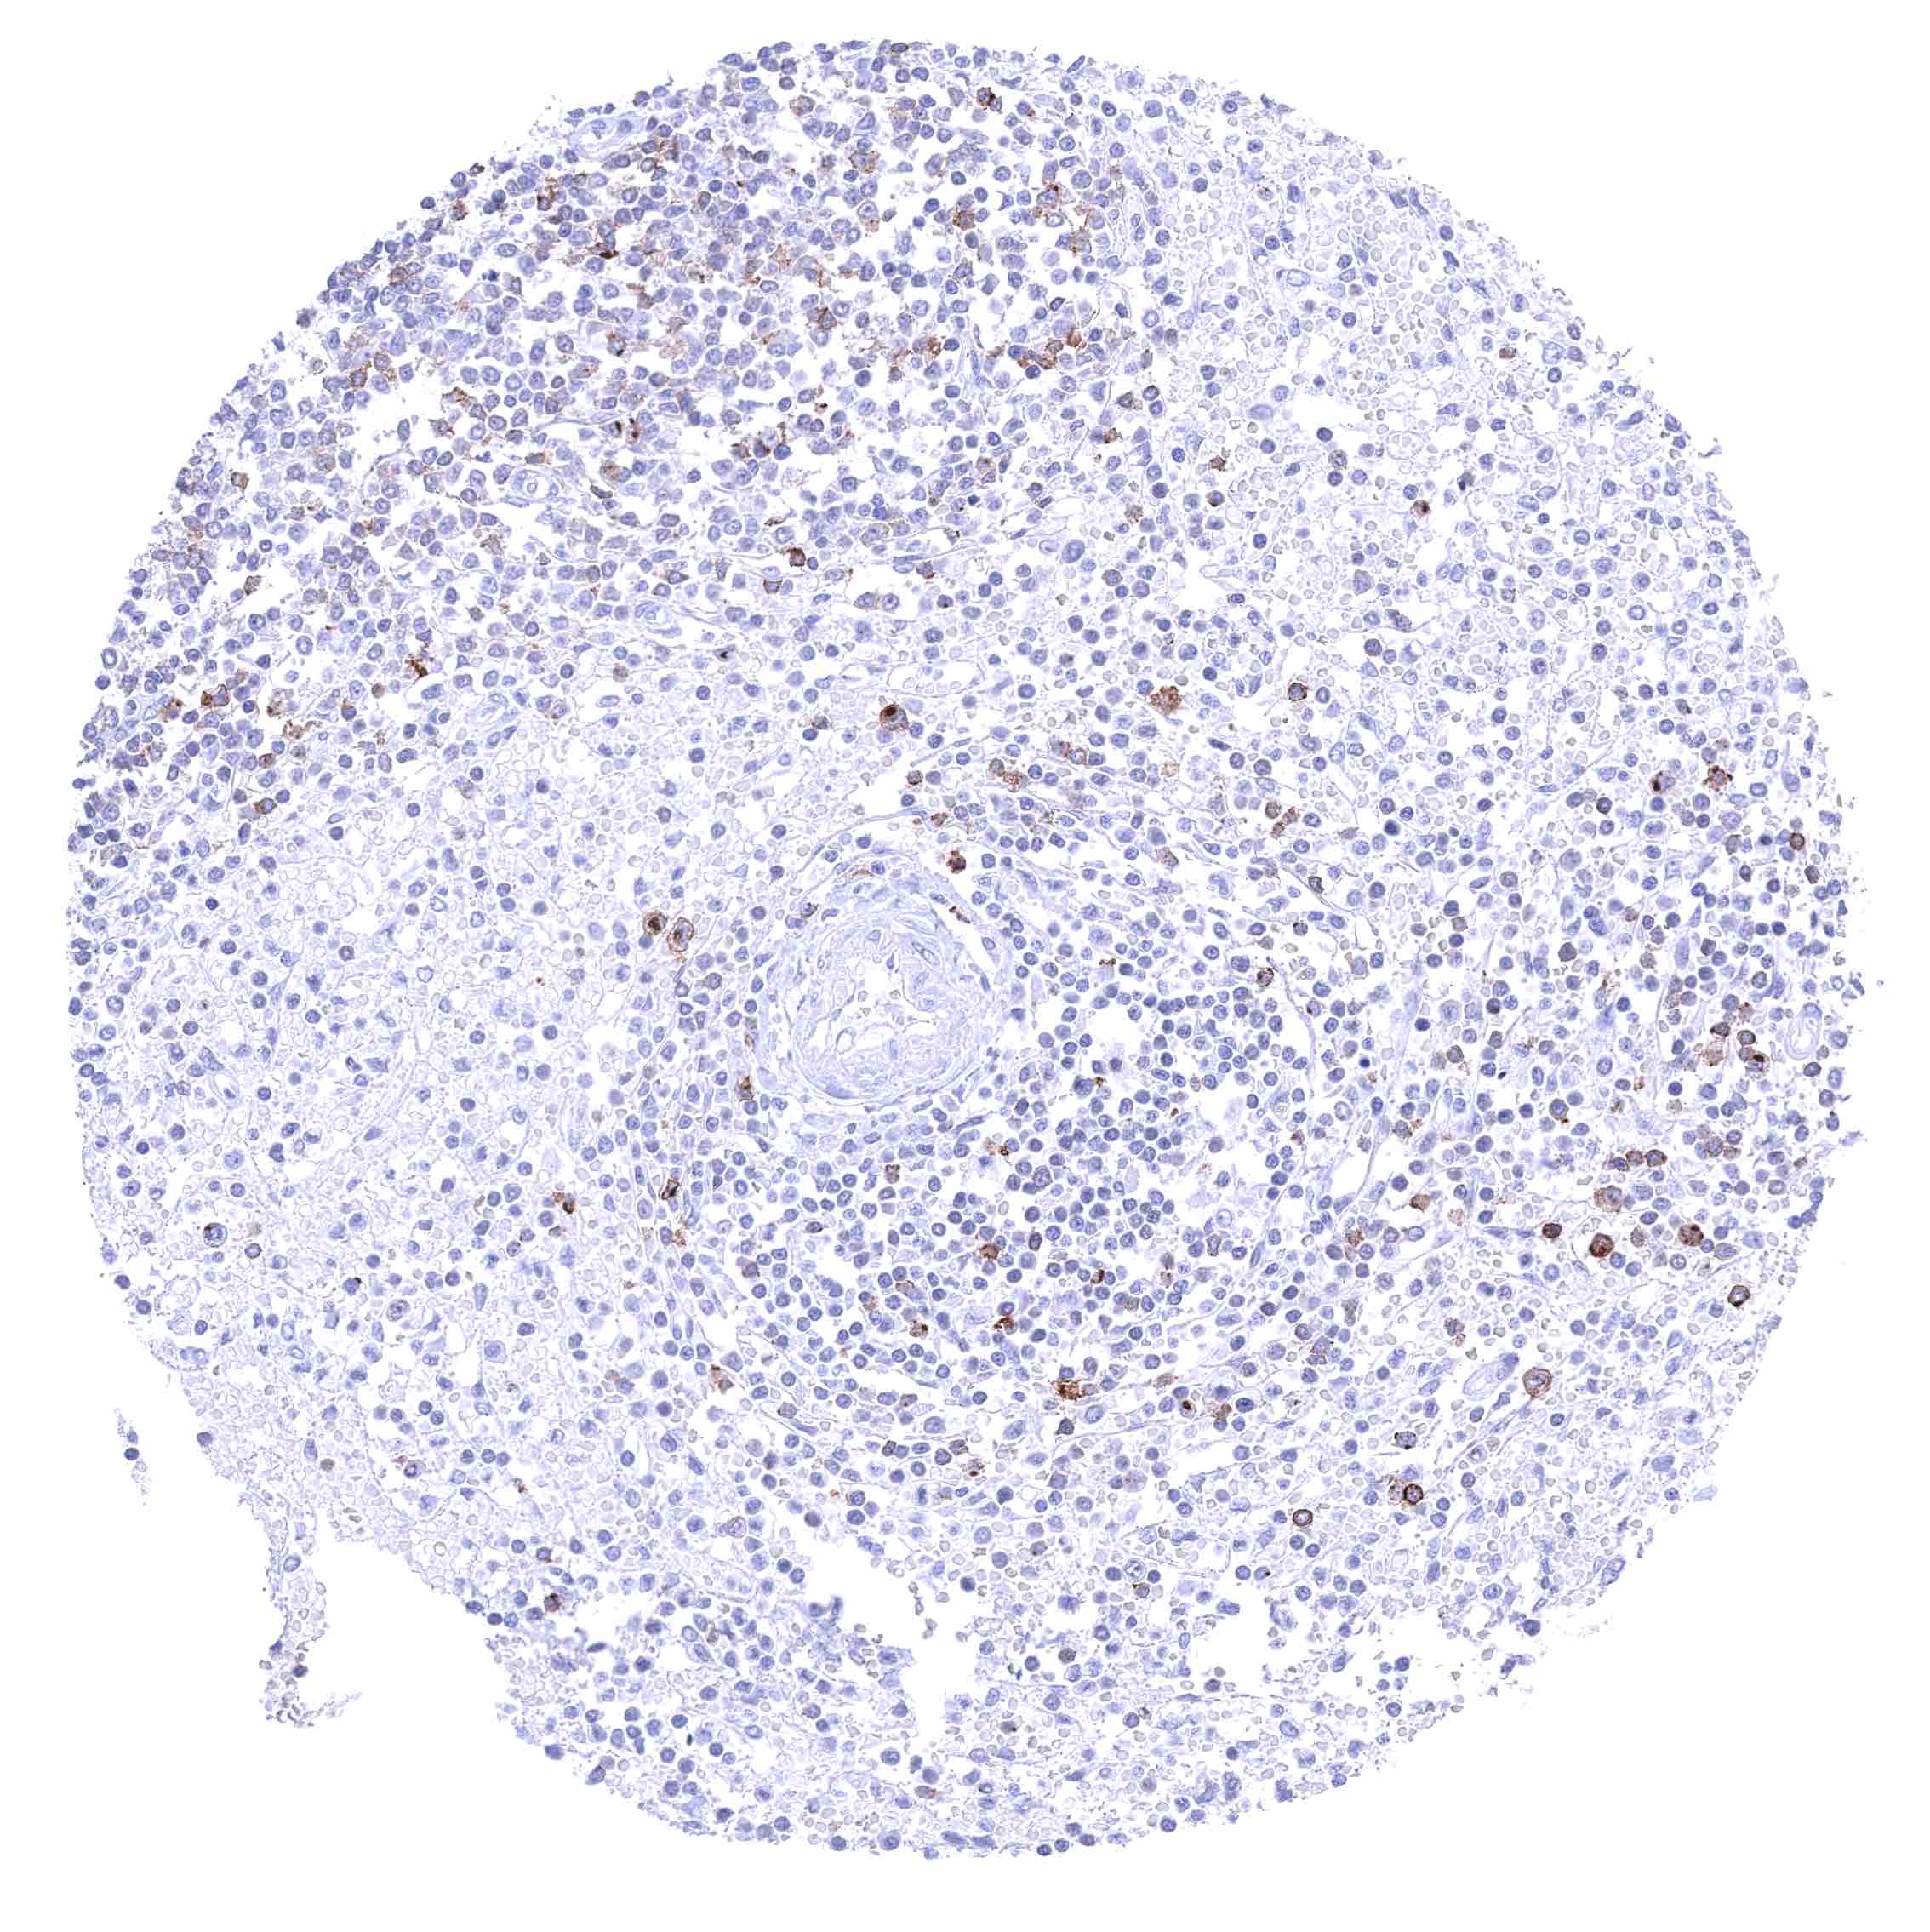

Lymph node – Membranous CD70 staining of variable intensity in subsets of cells (mostly lymphocytes). Most CD70 positive cells are interfollicular.